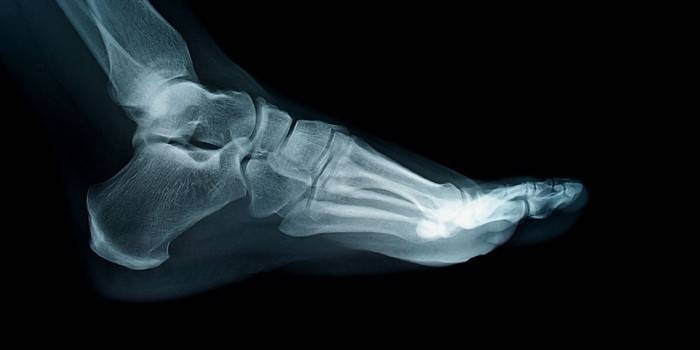

- Raio-X para determinar a área de dano.

Foto do salto da bursite